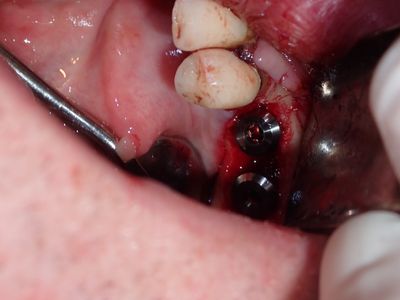

Bone loss noted, bone graft required, upon flapping, decided to place implants. Difficult case due to very strong macroglossic tongue, limited sulcular space. Short and wide implants placed, all socket/defects grafted with sticky bone from cortical allograft. membrane placed interimplant and fibrin membrane also used